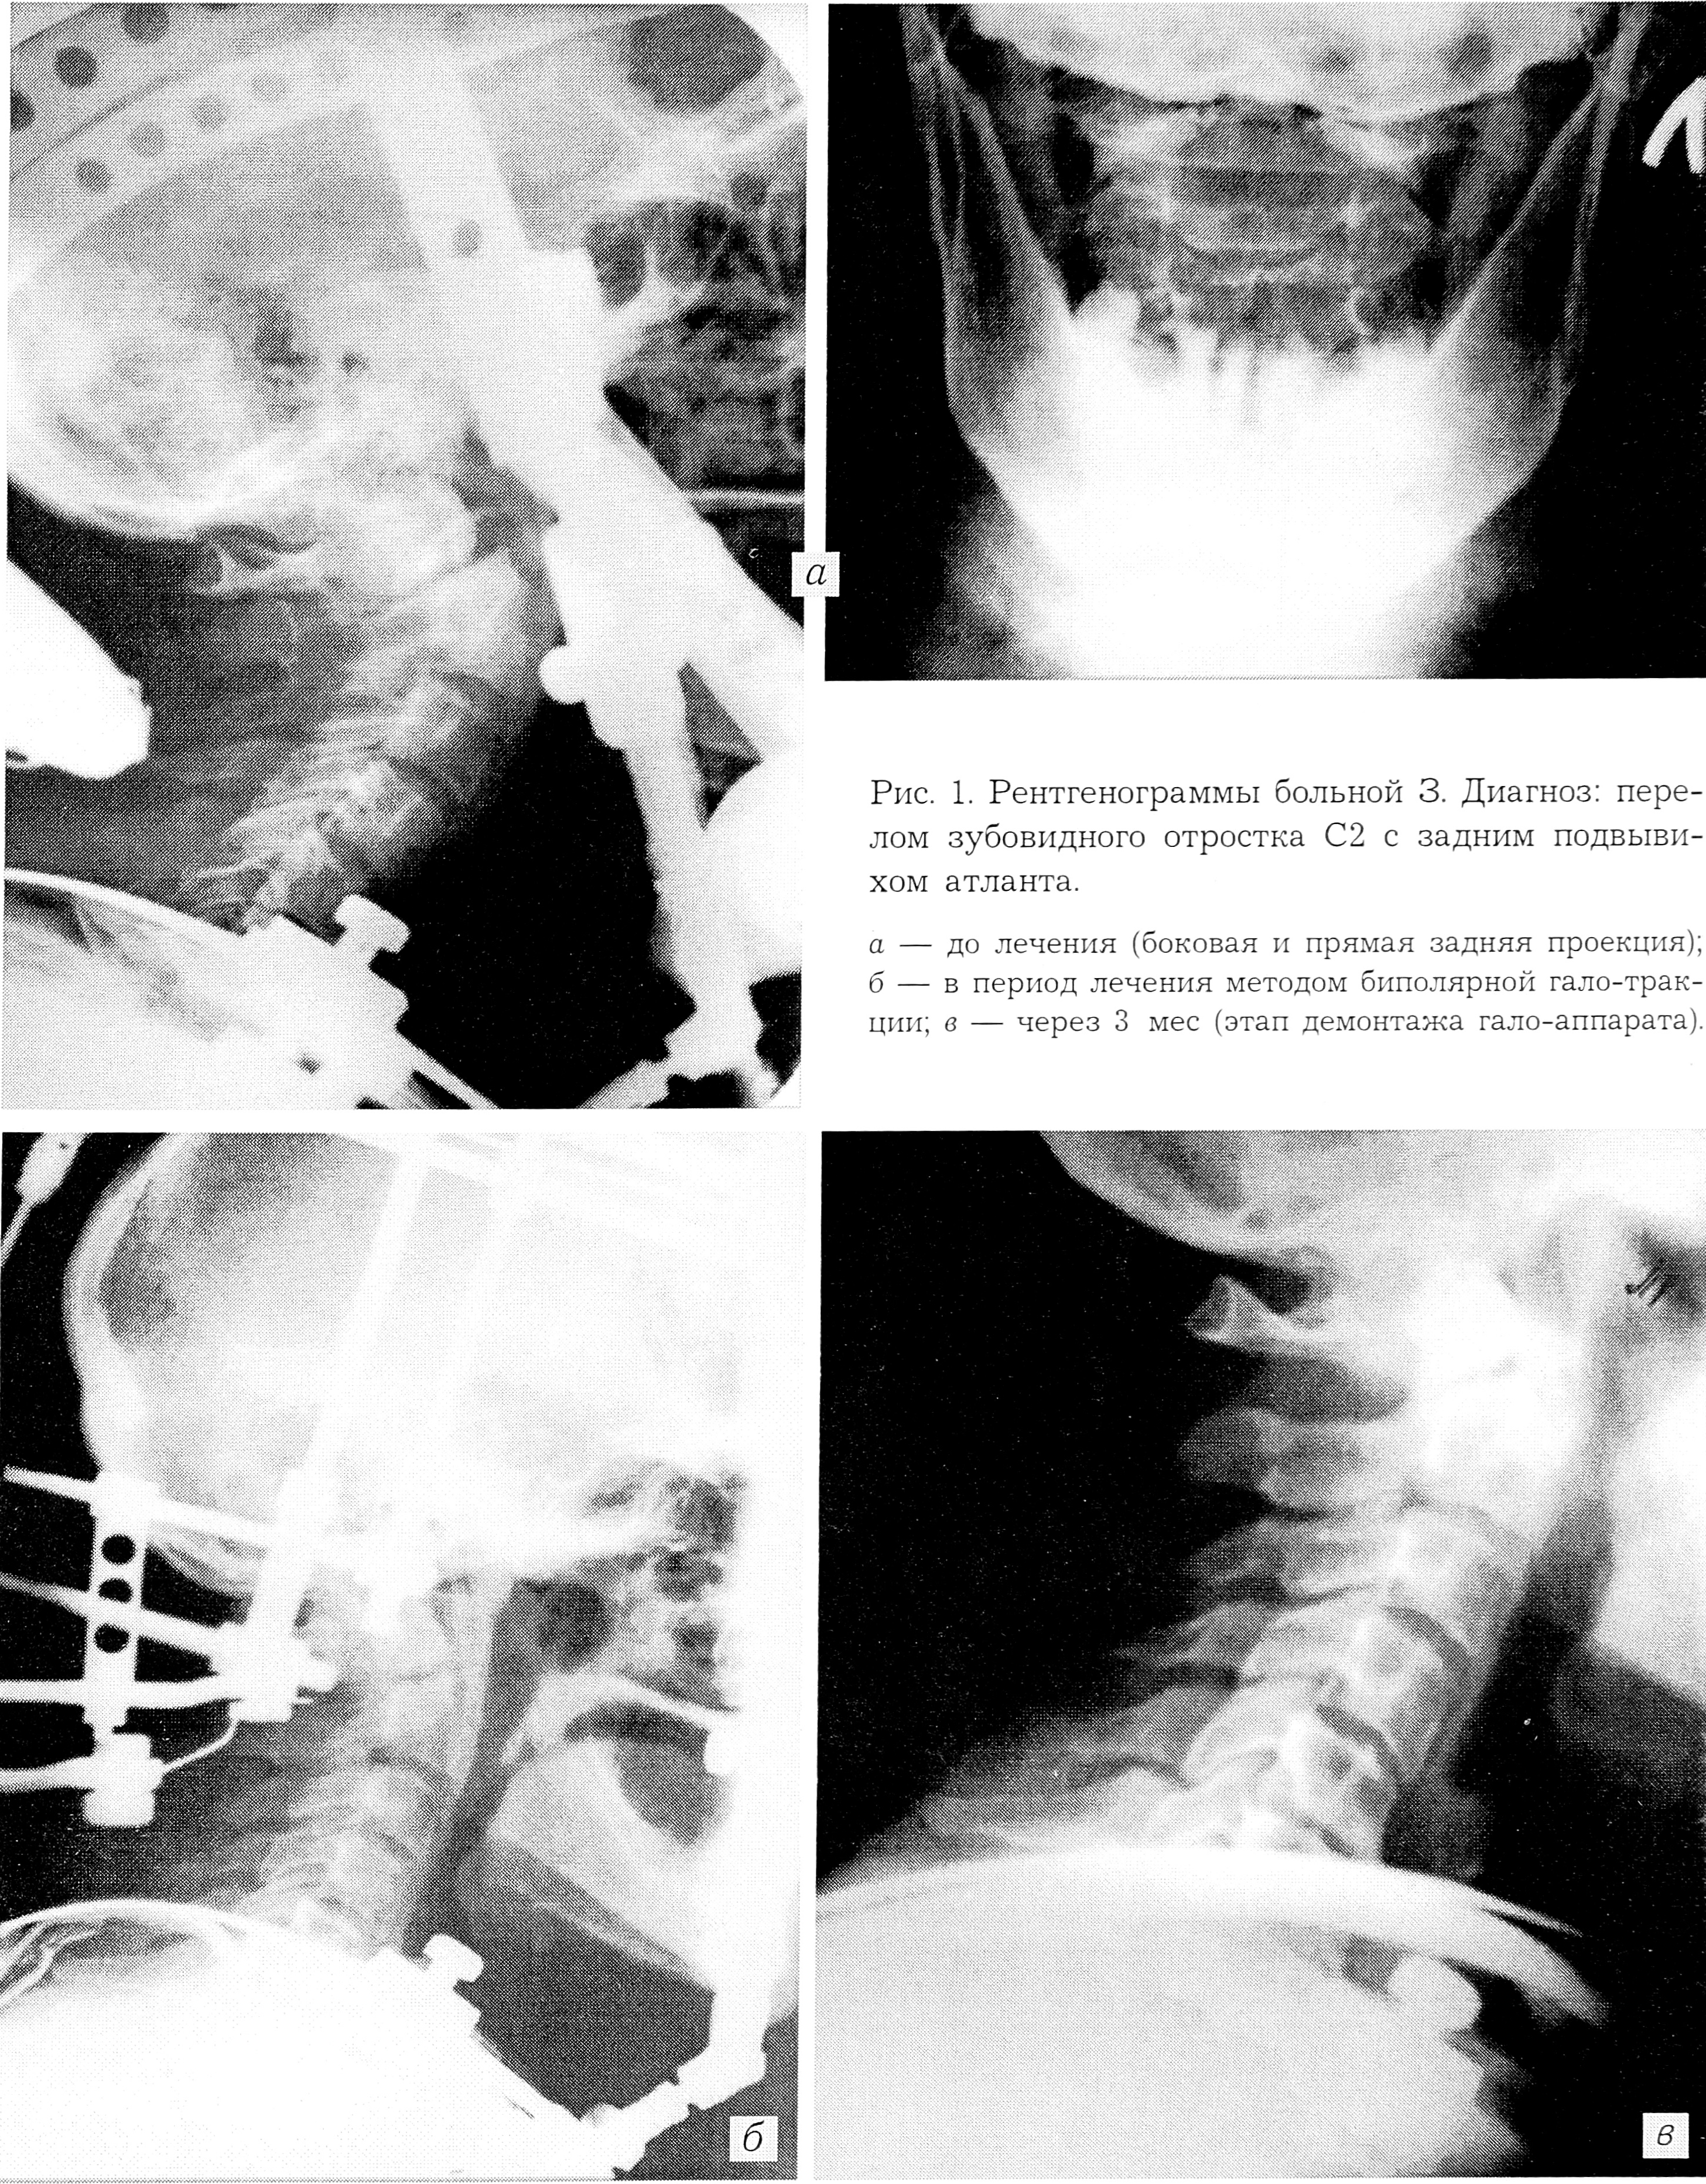

Больная 3., 72 лет, поступила через 2 дня после получения травмы (упала, поскользнувшись на льду). Кроме резких болей в верхнешейном отделе позвоночника с ограничением движений головы, появилась дисфагия, изменился голос. Отмечалось снижение силы в левой руке. На спондилограммах верхнешейного отдела позвоночника в двух проекциях, выполненных в иммобилизирующем устройстве (см. рис. 1, а на вклейке), выявлен базальный перелом зубовидного отростка С2 со смещением назад на 3/4 его диаметра. Диагноз: перелом зубовидного отростка с задним подвывихом атланта; ушиб бульбарного отдела продолговатого мозга. Назначена нейротропная терапия. 27.03.90 выполнен первый этап операции — создание биполярной гало-тракции шейного отдела позвоночника. После осуществления репозиции путем дозированной тракции 20.04 произведен второй этап операции — создание блока чрескостной фиксации С2 позвонка. Смещение зубовидного отростка в пределах 1/3 его диаметра (рис. 1, б). Гало-аппарат демонтирован 22.06 (через 3 мес) при наличии костно-фиброзного сращения перелома зуба С2 (рис. 1, с). Обследована через 2 года — 20.02.92 (см. рис. 2 на вклейке). Двигательный сегмент С1—С2 стабилен. Обслуживает себя самостоятельно.

Рис. 2. Функциональные рентгенограммы больной З. через 2 года после травмы.